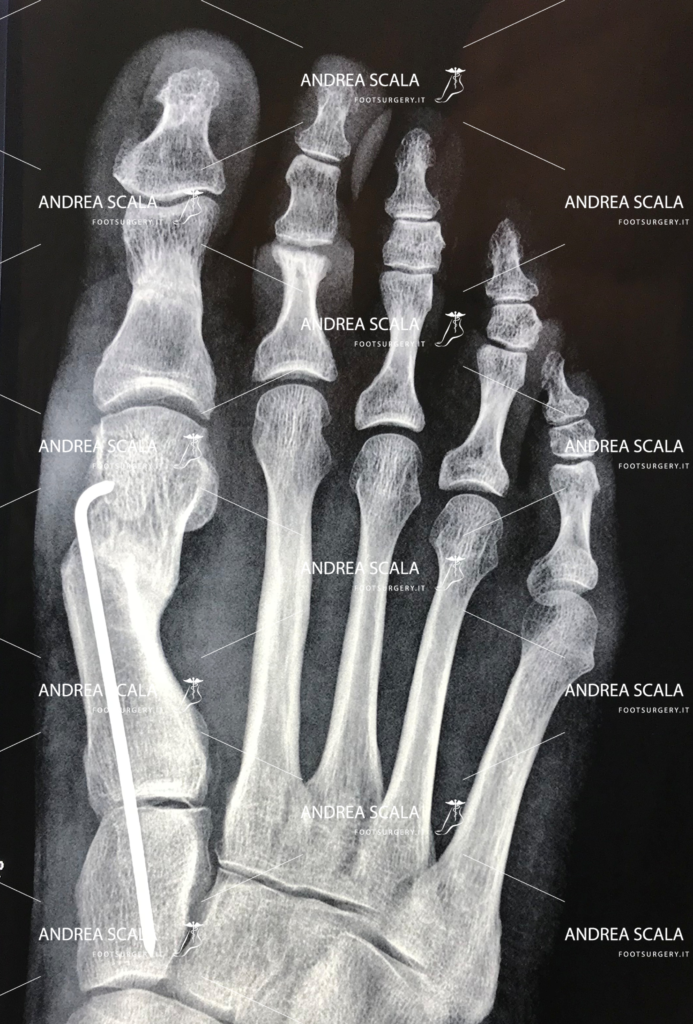

Dopo aver eseguito l’osteotomia (intervento chirurgico di taglio dell’osso) del 1° metatarso viene corretta la disposizione delle ossa, dei legamenti, dei tendini e dei nervi, con il conseguente riallineamento dell’alluce rispetto alle altre dita del piede. A questo punto si introduce all’interno un sottile filo metallico (1,5 mm). Non si mettono fili metallici esterni tipo “spiedino”. Il filo metallico interno fornisce la garanzia che l’alluce operato non tornerà mai più in valgo. Il dato saliente che caratterizza l’intervento è che la testa del 1° metatarso viene esattamente posizionato sopra i due sesamoidi. Pochi altri interventi hanno la medesima accuratezza, nessuno con tecnica percutanea.

L’aspetto più importante è il grande spostamento in senso laterale della testa del 1° metatarso, questo fa sparire la “cipolla” di più e meglio degli altri interventi. Rimuovendo lo spostamento patologico del 1° metatarso, in corrispondenza della “cipolla”. Il piede assume la forma desiderata dalla paziente.

Dopo la prima visita, vengono effettuate tutte le indagini diagnostiche del caso che possono portare o meno all’operazione. La prima visita è indicativa per il medico che potrà osservare il paziente in posizione eretta e durante la deambulazione, concentrandosi su appoggio di avampiede e retropiede. L’esame radiografico dei due piedi sottocarico è di fondamentale importanza. In alcuni casi può essere opportuno effettuare anche altri esami come Tac, Risonanza magnetica o Ecografia.